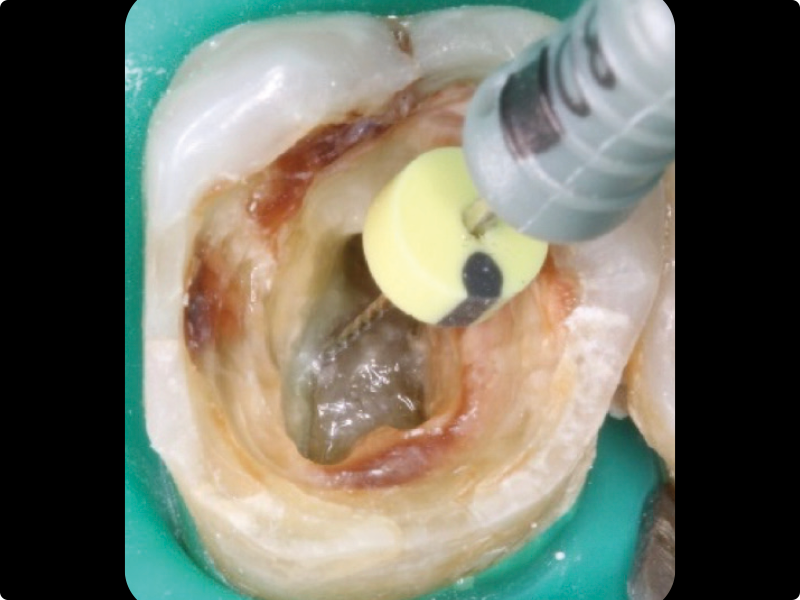

• Endodontic retreatment: why, when, and how to retreat.

• Redefining a proper access cavity.

• Removal of intracanal retainers: metal posts, fiber posts, zirconia posts.

• Removal of root canal filling materials.

• Retreatment of the teeth filled in the previous practical session.